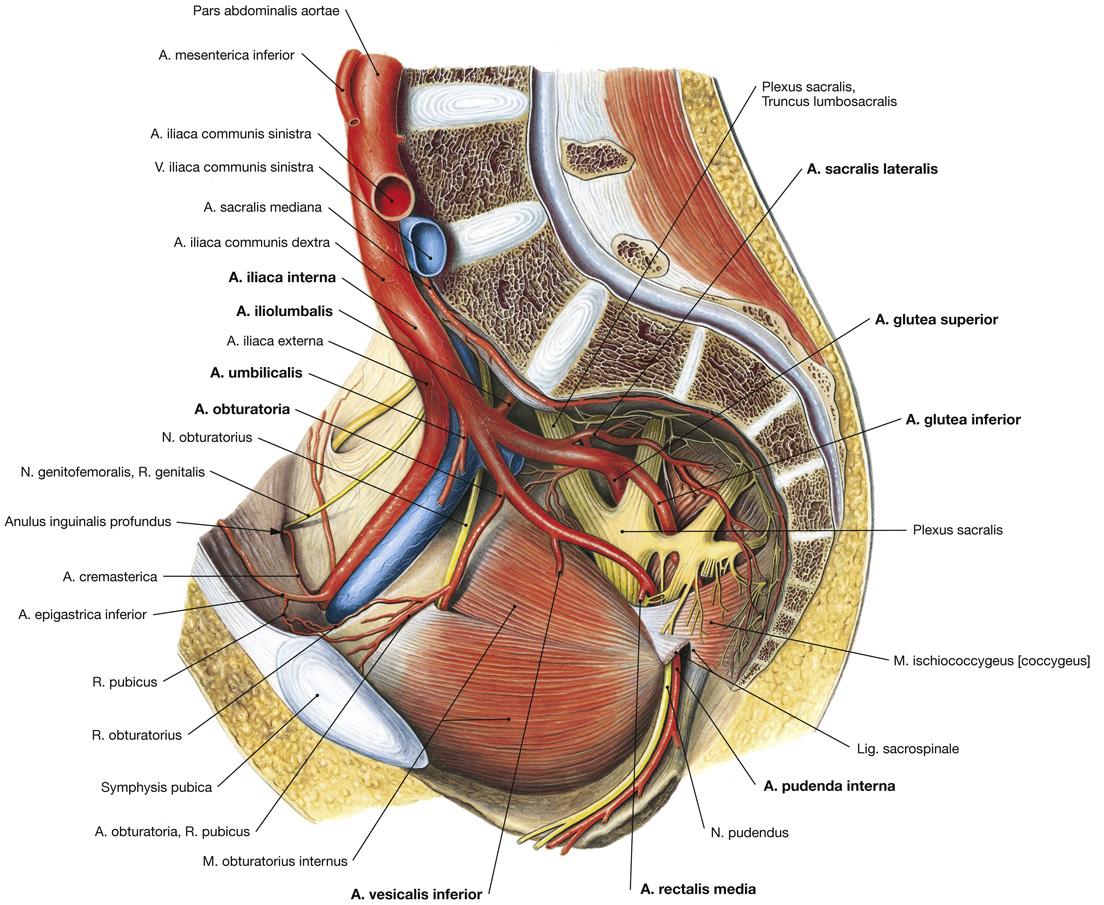

Fig 3.27: a. iliaca interna - dorsale hoofdstam

A doorsnede

os pubis sacrum -

a iliolumbalis

a sacralis lateralis -

a glutea superior

r superficialis r profundus

B vooraanzicht

C zijaanzicht

os coxae > os ilium lig sacrotuberale -

lig sacrospinale

Fig 3.28: a. iliaca interna - ventrale hoofdstam

os pubis vesica urinaria (blaas) L5 sacrum -

a iliaca interna

dorsale hoofdstam -

ventrale hoofdstam